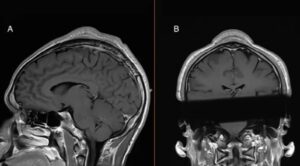

При этом мы не знаем гистологии удаленной в Витебске опухоли и не можем однозначно сказать, какого она характера. Это либо доброкачественная миома матки, либо злокачественная саркома. До получения гистологического ответа дифференцировать два состояния нельзя: на УЗИ миома и саркома выглядят одинаково.

В литературе известны случаи, когда опухоли матки достигали огромных размеров. В 2018-м хирурги-гинекологи в Сингапуре удалили миому, которая весила 28 кг. Но самая большая, которая была удалена и описана, весила 63 кг. В такое действительно сложно поверить, однако это факт.

– Потенциал миомы определяется клетками, из которых она образуется. Согласно статистике, доброкачественные миомы встречаются у 70-80 процентов женщин старше 40 лет. Они не всегда большие. Часто могут оставаться маленьких размеров (до двух сантиметров) и не увеличиваться на протяжении всей жизни. Если же при УЗИ мы видим, что размер узлов достигает 5-6 сантиметров, то это уже показание к лечению.